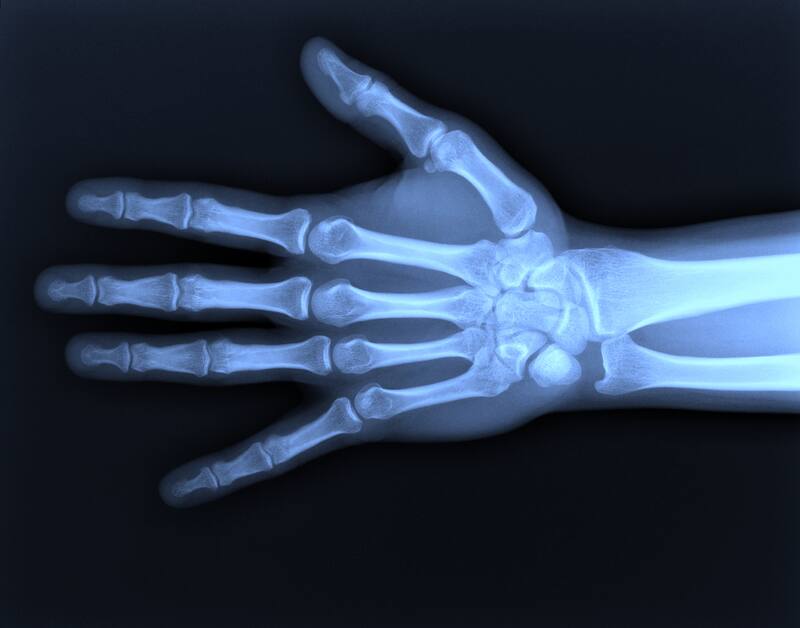

, entre los huesos se encuentra líquido sinovial, cuyo fin es reducir la fricción que se produce con el movimiento de estos. Este líquido cuenta con gases como oxígeno, nitrógeno y dióxido de carbono adentro. Cuando uno retuerce los dedos para sonarlos, se genera una presión que forma burbujas dentro del líquido sinovial. Estas explotan y son el resultado del ruido que escuchamos al sonar los huesos.

La mayoría de los estudios al respecto sostienen que no genera ningún mal realizar está práctica y que no genera mayor posibilidad de artritis en las manos. De hecho, un estudio realizado por un científico muestra que sonó los dedos de una sola mano por 60 años, mientras que en la otra no realizó el mismo ejercicio. En sus resultados, no notó más artritis en una mano que en la otra.

Sin embargo, un estudio de 1990 realizado en 300 personas sostuvo que sonarse los huesos por un gran período de tiempo tiene consecuencias: baja la fuerza a la hora de agarrar algo y puede traer hinchazón en las manos.